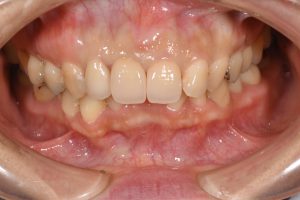

After

術後

歯肉の炎症による赤み、金属の土台による変色、天然歯との色の不調和を改善できた。